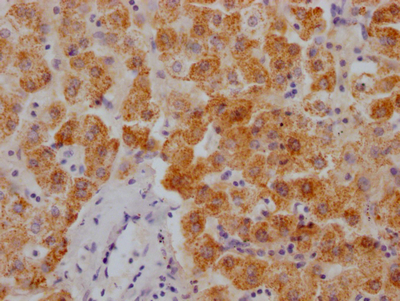

IHC image of CSB-PA896505DSR2HU diluted at 1:50 and staining in paraffin-embedded human Lung cancer performed on a Leica BondTM system. After dewaxing and hydration, antigen retrieval was mediated by high pressure in a citrate buffer (pH 6.0). Section was blocked with 10% normal goat serum 30min at RT. Then primary antibody (1% BSA) was incubated at 4°C overnight. The primary is detected by a Goat anti-rabbit polymer IgG labeled by HRP and visualized using 0.05% DAB. Secondary antibody only control: uses 1% BSA instead of primary antibody